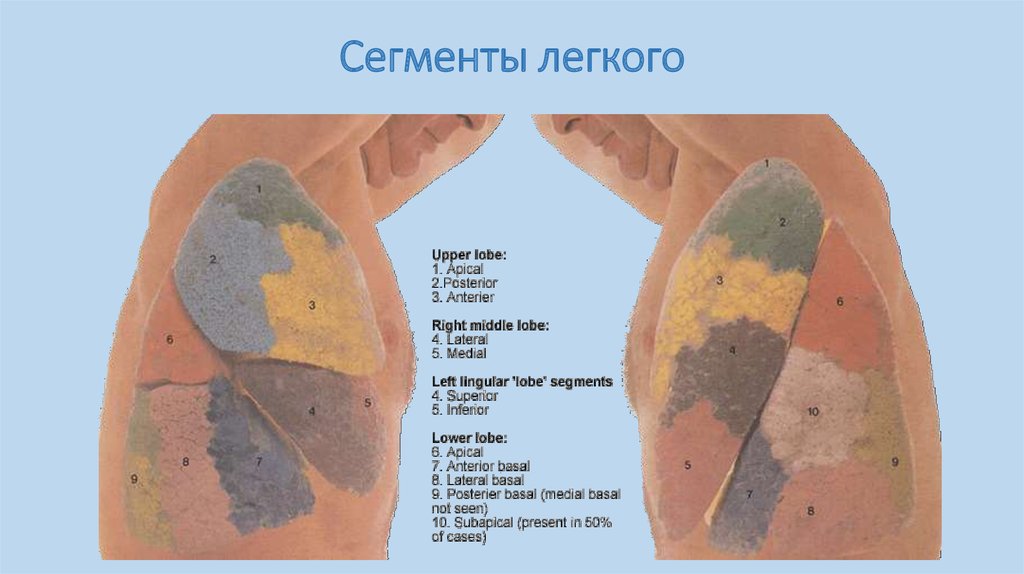

Анатомические изображения сегментов легких различных животных

Раздел: Другие животные